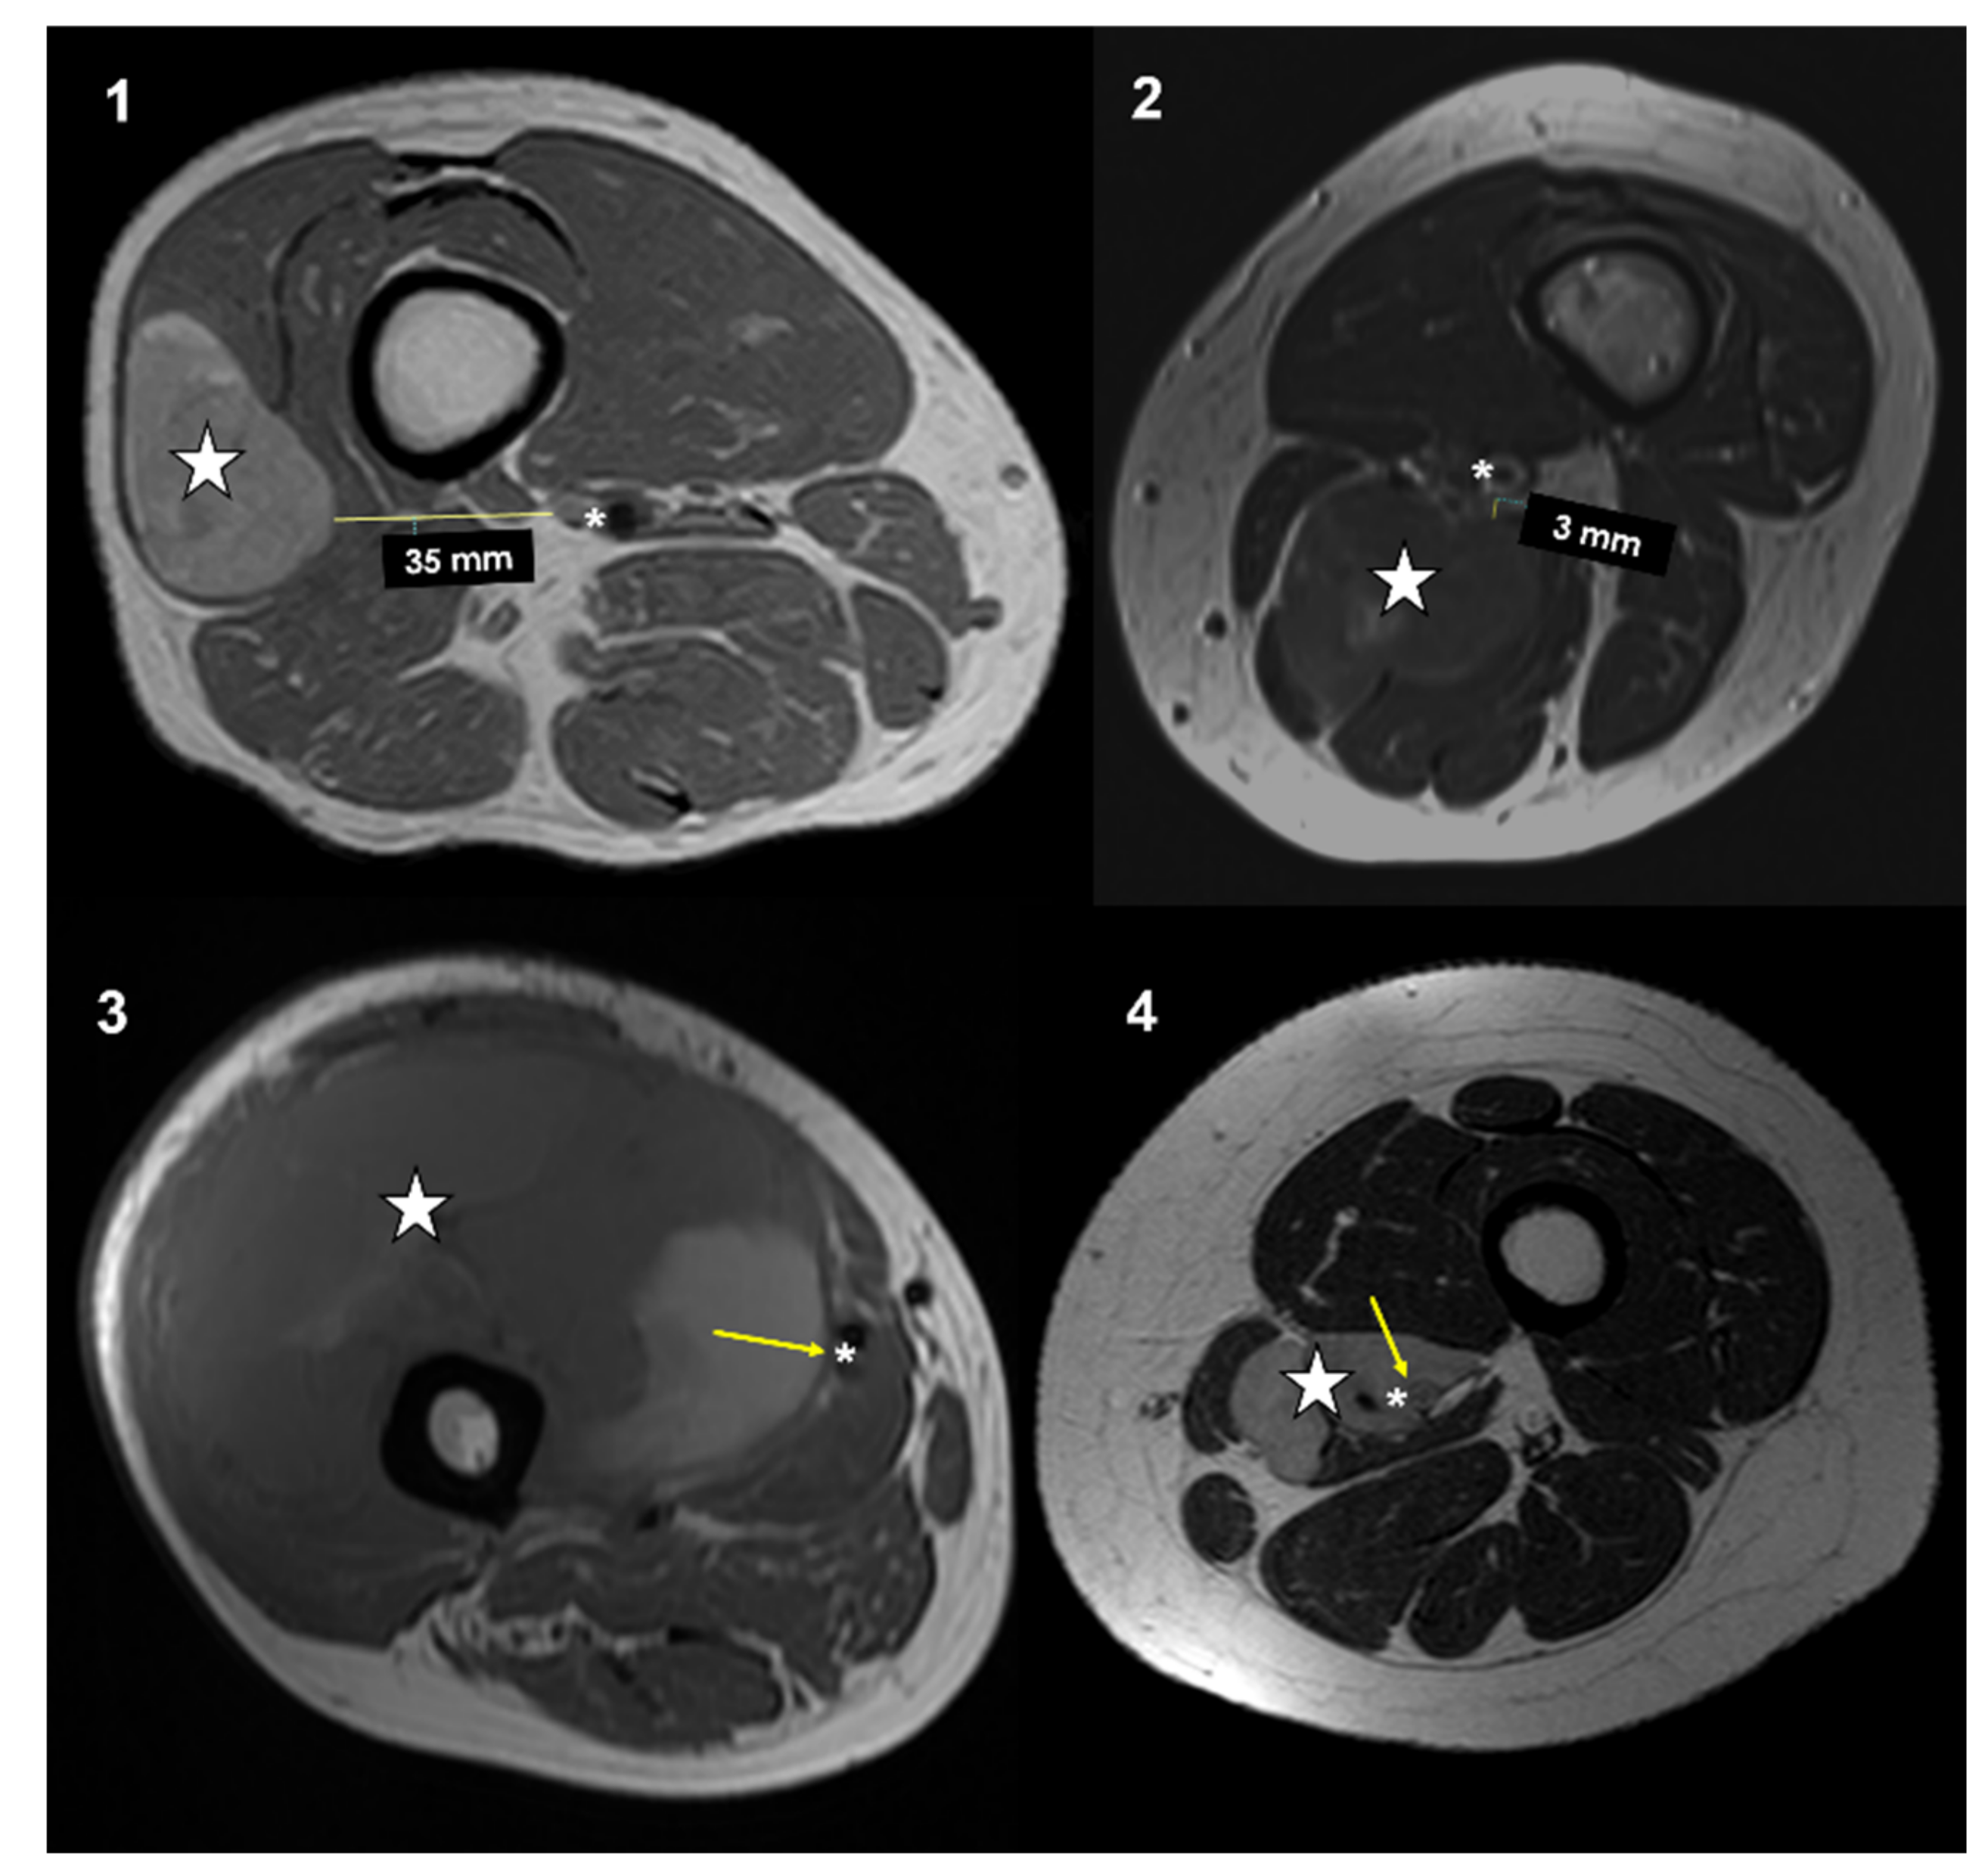

All patients had an MRI performed within a maximum of 21 days prior to surgery. All MRI were performed with a high field (1.5 Tesla or higher) and with the standard sequences, which included T1w, T2w, STIR, or T2 fat sat. Magnetic resonance imagines were retrospectively reviewed on a PACS (Carestream Vue PACS v. 11.4.1.1102) by two expert oncologic radiologists (PS and FP). Imaging analyses were performed in consensus. The closeness to major vessels was defined as the minimum distance between the tumor and the main vascular bundle. This distance was measured on the axial slices of preoperative T1-weighted MRI [19]. Distance between the major vascular bundle and the tumor was classified into four types according to Fujiwara et al. [15]: type 1, >5 mm; type 2, ≤5 mm and >0 mm; type 3, attached to the tumor; type 4, surrounded by the tumor (Figure 1).

Types of vascular proximity based on MRI T1w axial images performed in four different patients affected by soft-tissue sarcomas of the thigh and popliteal fossa: type 1: >5 mm; type 2: >0 mm and <5 mm; type 3: in contact; type 4: surrounded. Stars (neoplasms), asterisks (main vessels), arrows (tumor-vascular contact).